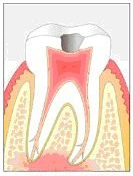

In Abb. 2 ist das Röntgenbild 22 Jahre nach korrekter Wurzelbehandlung mit dem nun überkronten Zahn zu sehen. Der Knochen um die Wurzelspitzen ist entzündungsfrei gesund.